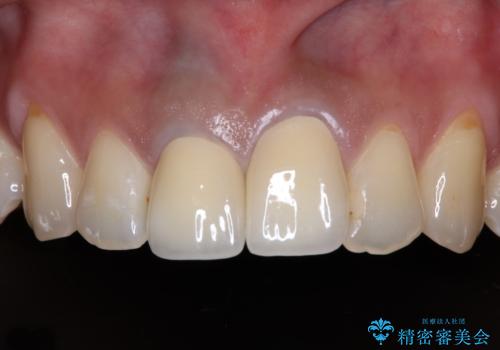

オールセラミッククラウンは金属を使用していないため、本物の歯のような綺麗な仕上がりとなりました。